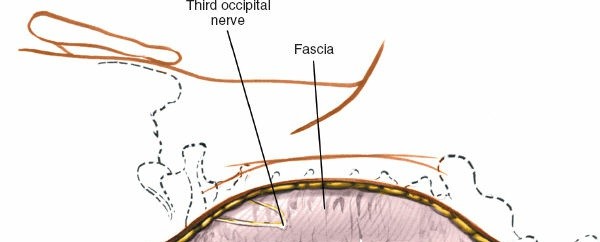

The posterior approach is utilized for highly unstable injuries requiring robust biomechanical stabilization, irreducible facet dislocations, or multilevel posterior compression (e.g., central cord syndrome with congenital stenosis).

* Exposure: Subperiosteal dissection of the paraspinal musculature is performed laterally to the lateral mass margins.